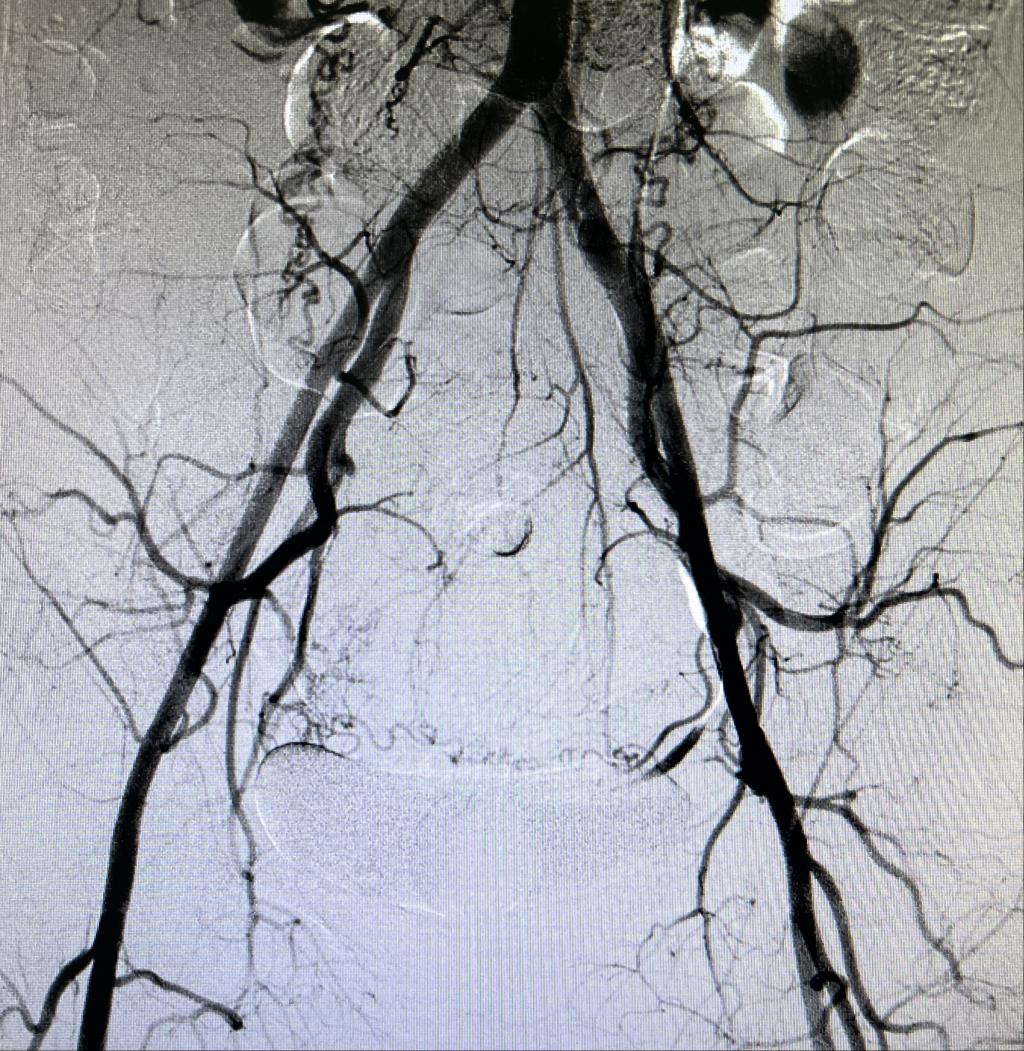

患者王某,女性,38岁,瘢痕妊娠二月余药流+清宫术后大出血,出血量2000ml以上。正值晚21时,各术室满台,主治医师谢纱将急会诊情况上报给主任后,科室同事积极配合,立即开通DSA第二夜间绿色通道进行危急重患者介入手术。

为有效避免介入术后患者截石位清宫导致股动脉穿刺口血肿或假性动脉瘤的发生,患者平卧24小时绝对制动,选择经肱动脉(右上肢)穿刺,术中患者休克血压(80/55mmHg),又增加了穿刺难度。谢纱精准穿刺右肱动脉成功,经盆腔血管造影后明确子宫出血动脉即行超选择栓塞。术闭出血立止、术后生命体征平稳。